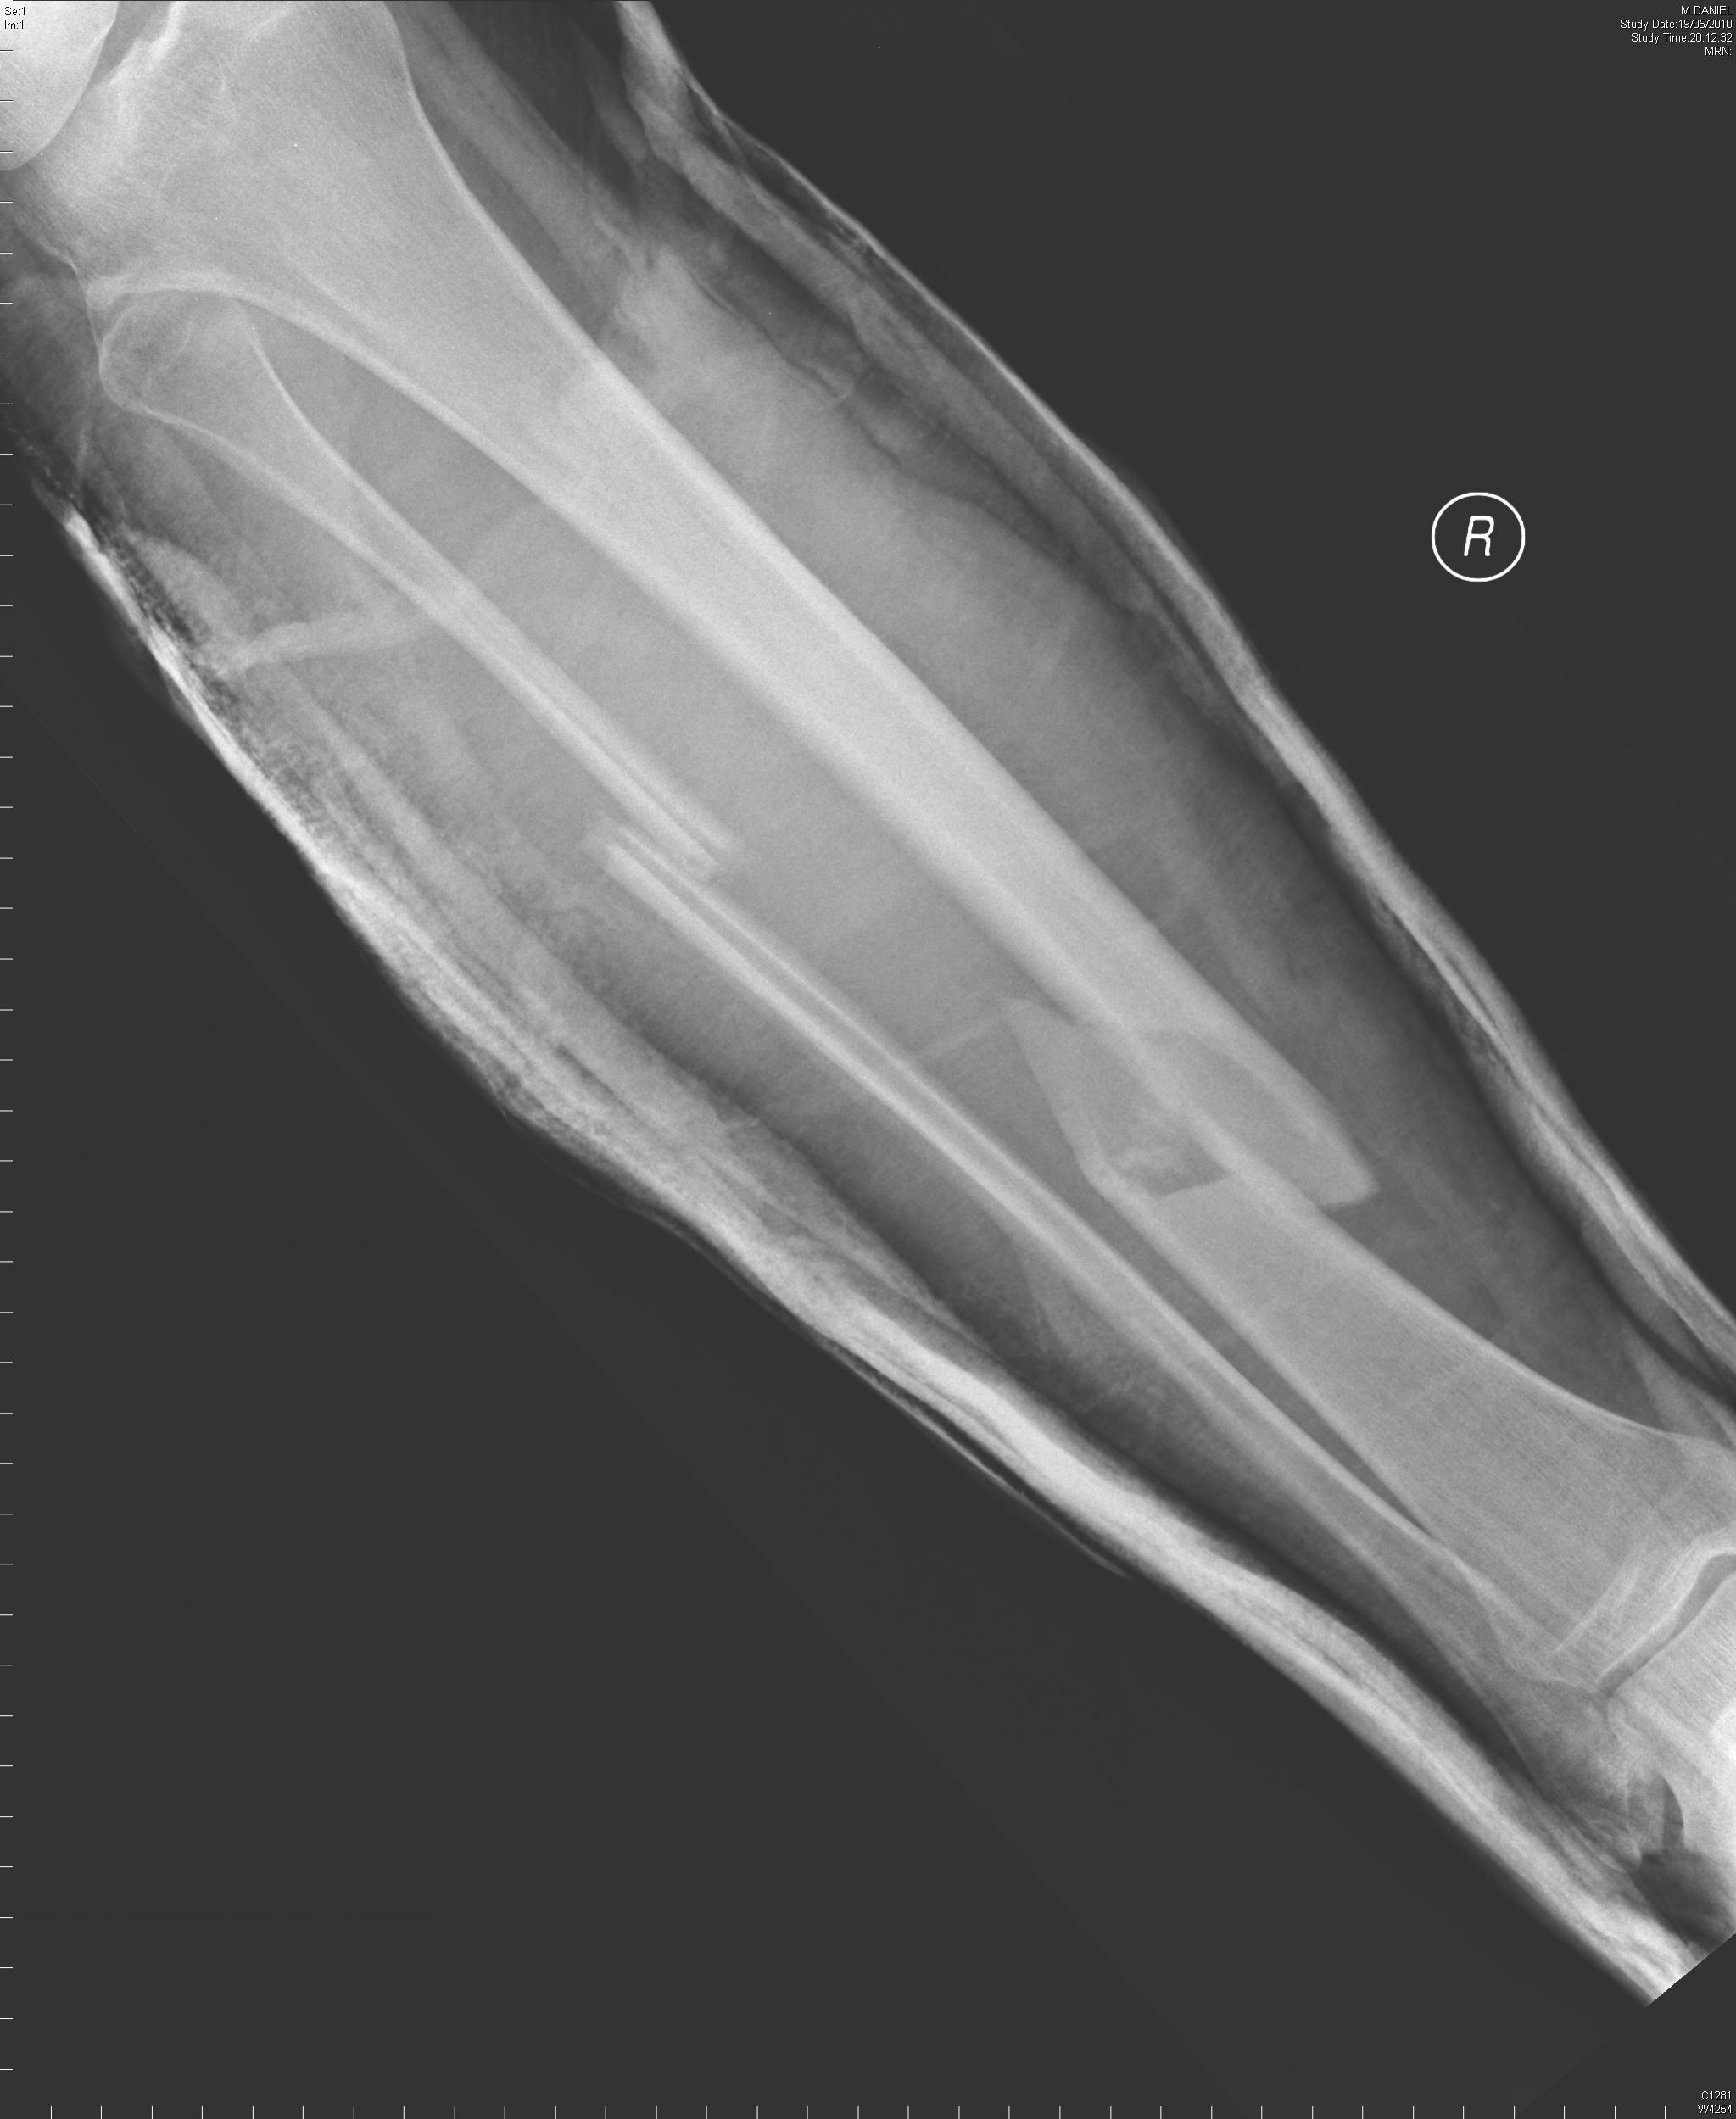

If it'll post on here, this is my x-ray AFTER they spent some time with the traction machine & sedatives...

They never sent one of the finished job, but take it from me it's gonna be worth a fair bit at the scrapyard after I'm gone!

The upshot of all that lovely experience is they managed to save my lower right leg eventually after some concern about the blood supply being cut off for over an hour (it took them ages to sedate me enough for my calf muscles to relax & let them pull the bones roughly into line!) and on the evening of the 21st May they got the drills & hammers out & put my leg back together with steel bars & big screws.